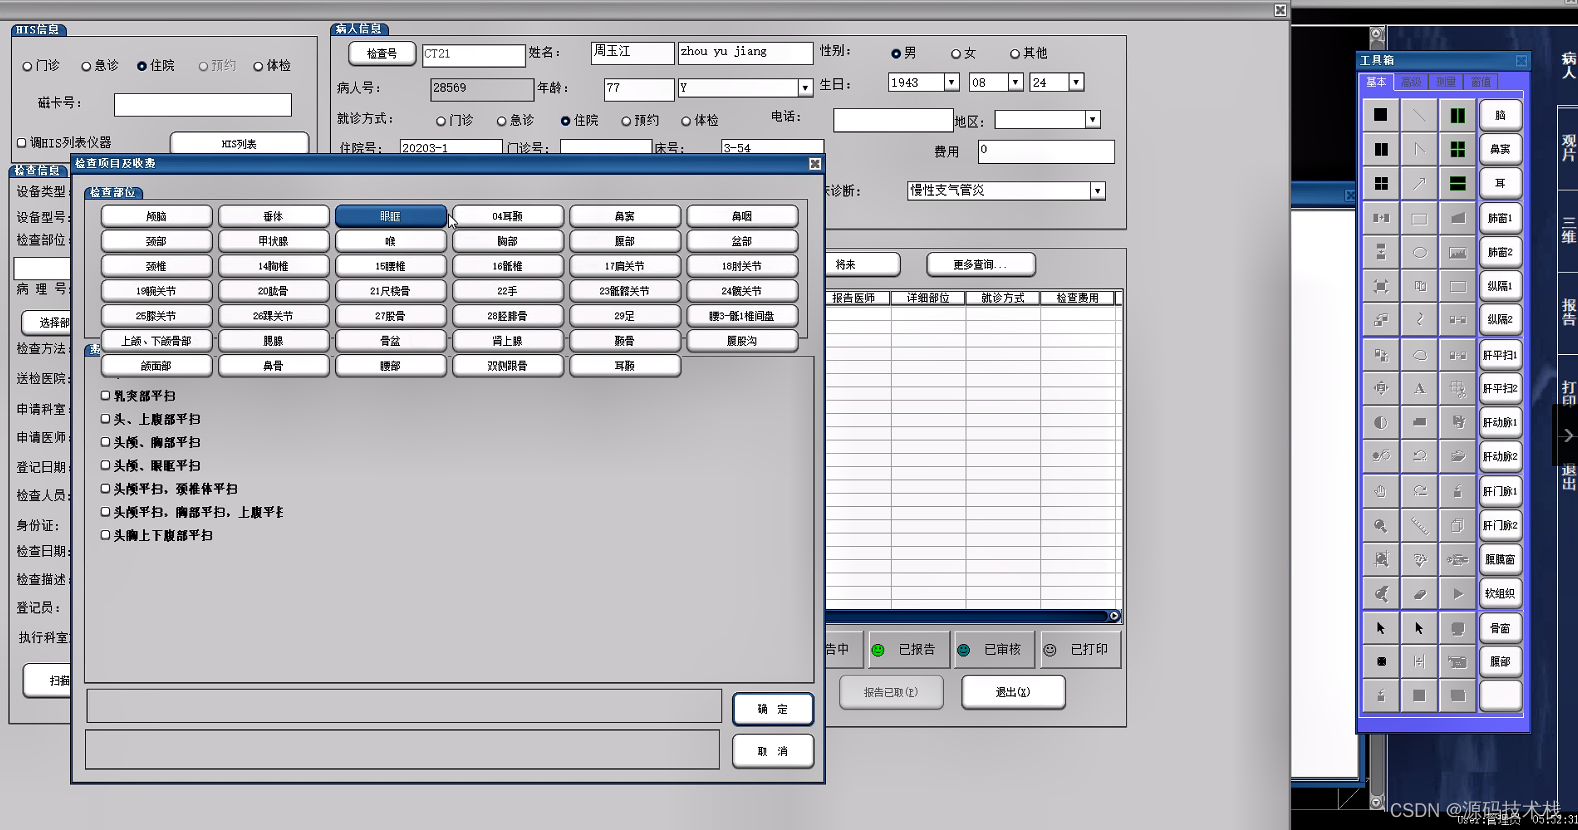

PACS主要包括图像获取、图像传输、图像储存和管理、图像影像工作站进行阅读四个流程。临床上,PACS系统流程从患者在登记台登记检查开始,然后患者进入检查室,技师进行检查,采集影像数据,将采集的影像数据进行上传至PACS网,影像医师通过PACS调阅图像并书写报告,最后将PACS的图文报告归档。

2、RIS

放射信息管理系统。主要有登记预约、排队叫号、技师模块、报告模块、主任模块、采集模块等模块。